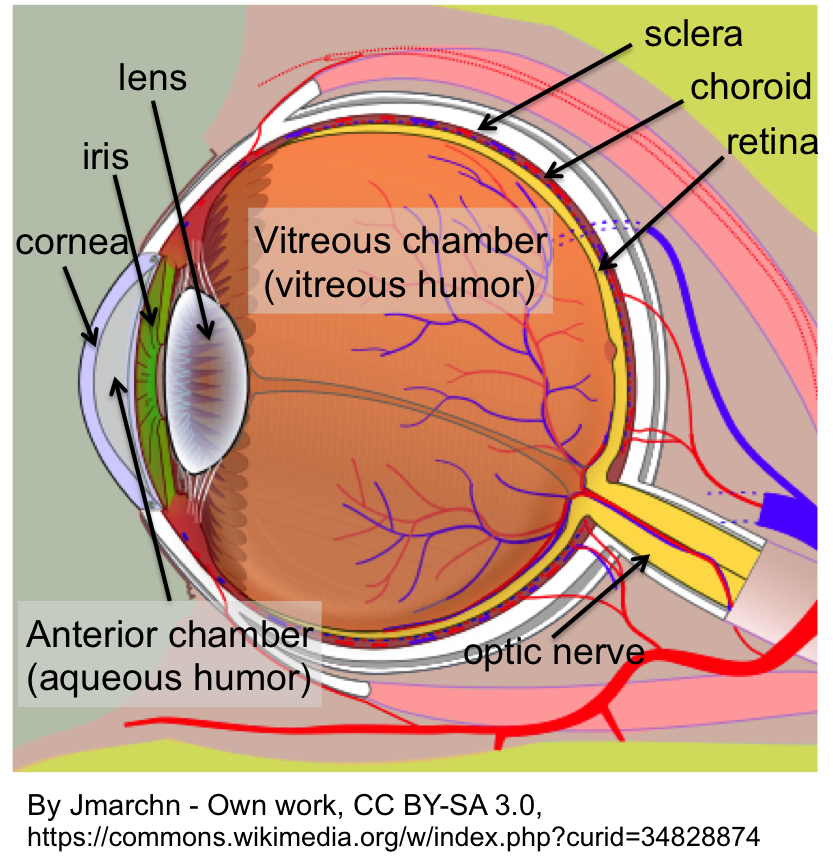

Biology-How our eyes work – Howthingswork.org

1 Anatomy of the Vitreous, Retina, and Choroid | Ento Key

Lab 35: Eye Structure Flashcards | Quizlet